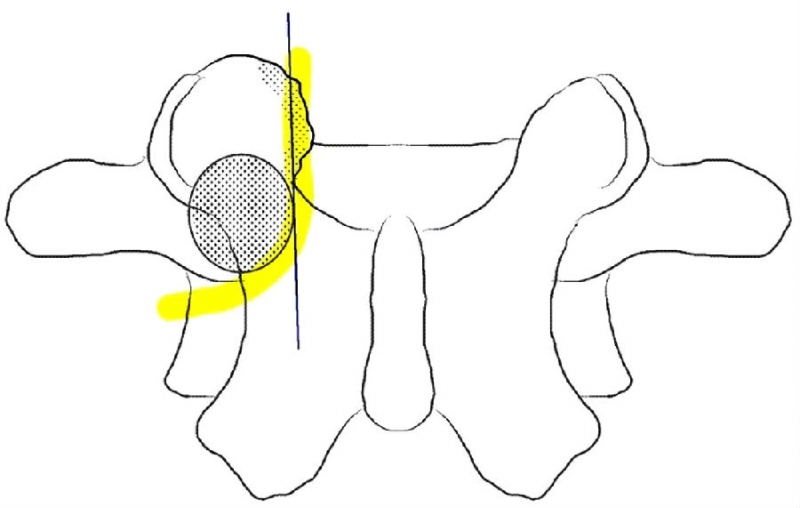

UBE处理椎管狭窄病例时,对于侧隐窝狭窄的患者,同侧减压范围与椎弓根内缘平齐即可。

从标本上看,椎弓根其实就位于终板的下方,这是术中判断椎弓根位置的解剖标志。

与椎间盘的下缘平齐即是椎弓根的上缘。

去除部分椎板上缘骨质尤其是与上关节突结合的部位利于黄韧带的切除及椎弓根内壁的显露。这个部位显露神经根的风险最小。